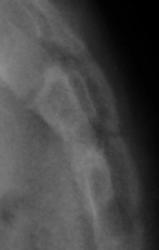

Ребенок направлен хирургом на рентгенографию крестца и копчика, Накануне ребенок упал. Приводится только боковая рентгенограмма, так как рентгенограмма, выполненная в прямой проекции не информативна.

Вопрос. Есть перелом или нет перелома?

Перелома нет

Валентин Львович! Мне видится межпозвонковый промежуток. Смещение по ширине отсутствует. Возможно такой вариант развития. Все таки изолированно сломать крестец у ребенка сложно.

Я тоже костно-травматических изменений не вижу.

Согласен с Ермолаевым, это межпозвонковый промежуток.